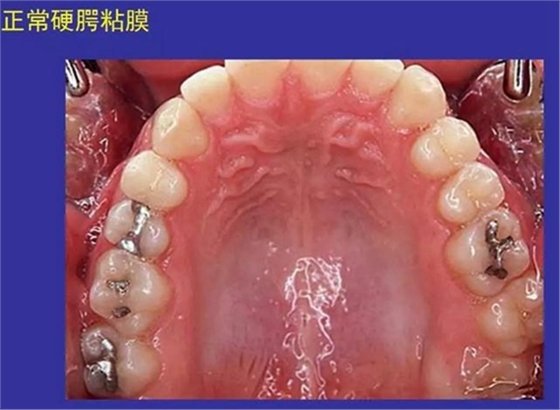

①口腔黏膜(oral mucosa):口腔內(nèi)的濕潤(rùn)襯里